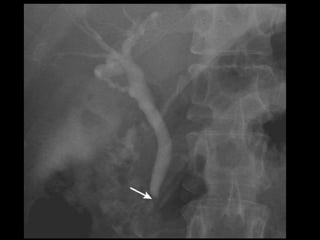

• Colangiografia

– CPRE: Diagnóstica e Terapêutica.

Vias Biliares • Funçãode carrear a bile do fígado para o duodeno. • Intra-hepáticas: 3mm • Bile é produzido continuamente pelo fígado e armazenada na vesícula. • Ductos hepáticos D e E > Ducto hepático comum. (3 – 6 mm) • Ducto Hepático Comum + Ducto Cístico > Ducto Colédoco. ( 8mm)

• 37.

Ducto Colédoco • 5– 15 cm • Finaliza seu percurso no duodeno (lado medial da porção descendente), passando posteriormente à cabeça do pâncreas. • Se liga ao ducto pancreático no meio do caminho formando a ampola hepatopancreatica (Vater), terminando na papila duodenal maior. (Esfincter de Oddi)